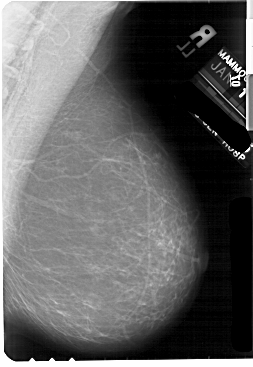

A_1869_1.LEFT_MLO

LEFT_MLO LINES 5491 PIXELS_PER_LINE 3781 BITS_PER_PIXEL 12 RESOLUTION 43.5 NON_OVERLAY